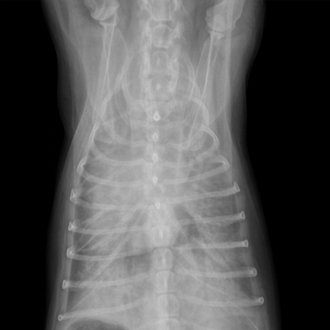

소화기계 응급

(위확장염전증)

위가 급격히 팽창·염전되며 생명을 위협하는 질환입니다.

시간 지연 없이 감압과 수술 여부를 결정해야 합니다.